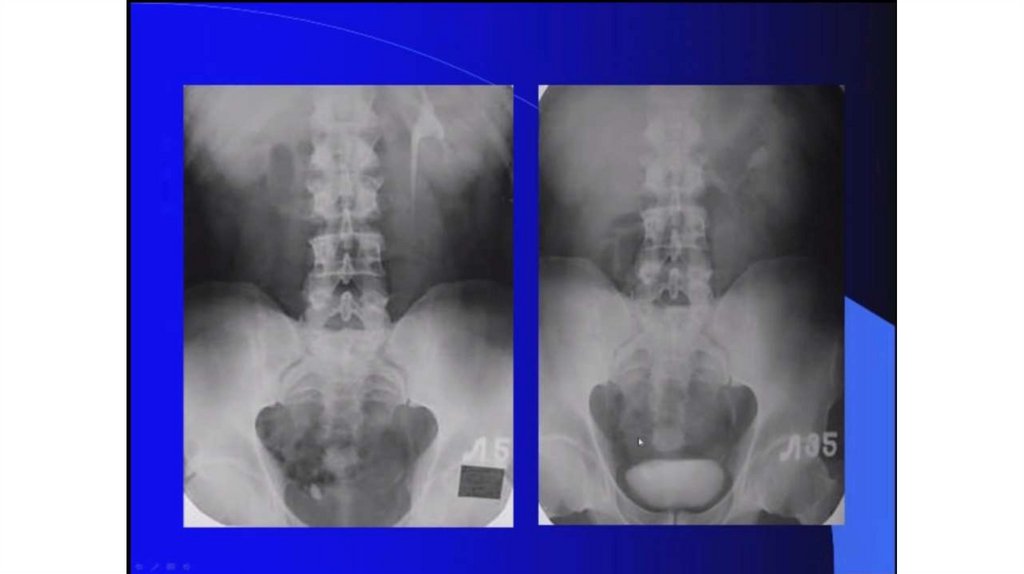

Мочекаменная болезнь. Мочекаменная болезнь и беременность

Мочекаменная болезнь